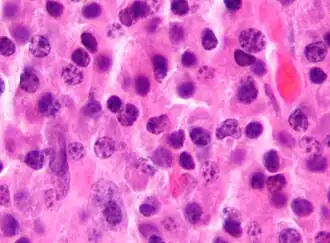

Bone marrow aspirate showing the histologic correlate of multiple myeloma under the microscope, H&E stain -

Plasmacytoma, H&E stain -

Histopathology

A bone marrow biopsy is usually performed to estimate the percentage of bone marrow occupied by plasma cells. This percentage is used in the diagnostic criteria for myeloma. Immunohistochemistry (staining particular cell types using antibodies against surface proteins) can detect plasma cells that express immunoglobulin in the cytoplasm and occasionally on the cell surface; myeloma cells are often CD56, CD38, CD138, and CD319 positive and CD19, CD20, and CD45 negative.[15] Flow cytometry is often used to establish the clonal nature of the plasma cells, which will generally express only kappa or lambda light chain. Cytogenetics may also be performed in myeloma for prognostic purposes, including a myeloma-specific fluorescent in situ hybridization and virtual karyotype.

The plasma cells seen in multiple myeloma have several possible morphologies. First, they could have the appearance of a normal plasma cell, a large cell two or three times the size of a peripheral lymphocyte. Because they are actively producing antibodies, the Golgi apparatus typically produces a light-colored area adjacent to the nucleus, called a perinuclear halo. The single nucleus (with inside a single nucleolus with vesicular nuclear chromatin) is eccentric, displaced by an abundant cytoplasm. Other common morphologies seen, but which are not usual in normal plasma cells, include:

- Bizarre cells, which are multinucleated

- Mott cells, containing multiple clustered cytoplasmic droplets or other inclusions (sometimes confused with auer rods, commonly seen in myeloid blasts)

- Flame cells, having a fiery red cytoplasm[43][44]